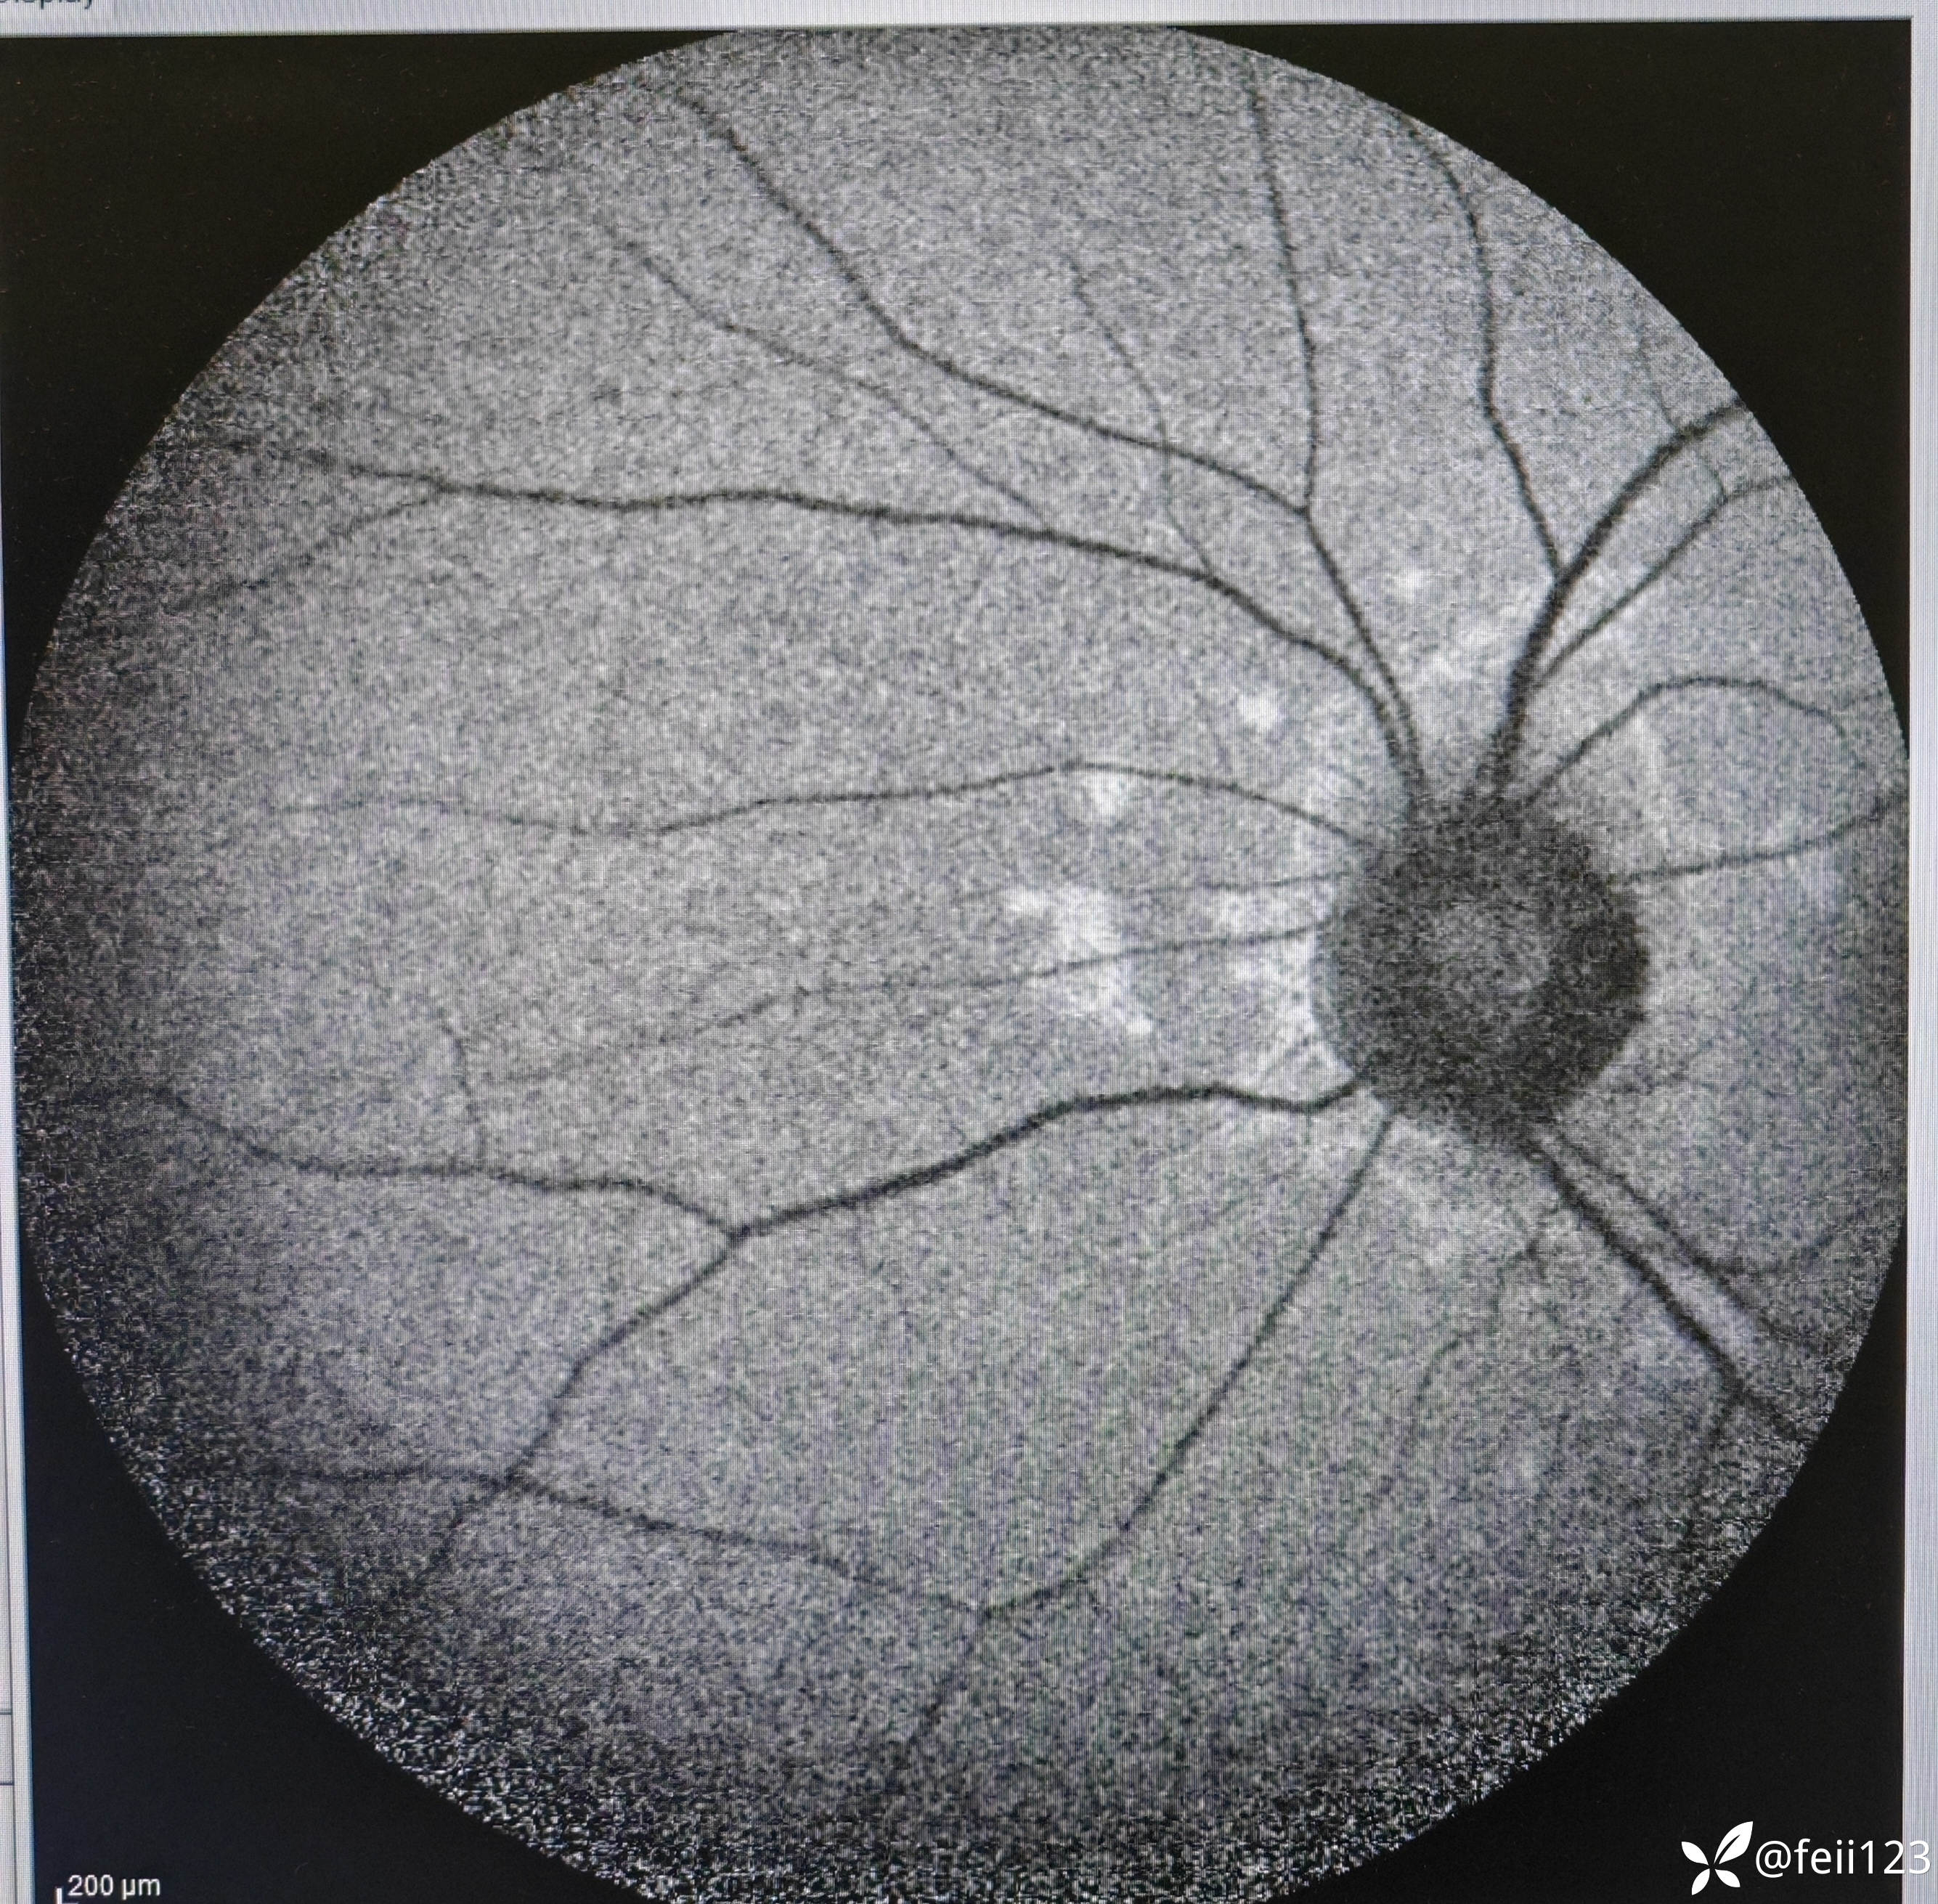

【检查】矫正视力右眼1.0左眼0.4,眼压正常15 16,眼前段未见异常,玻璃体清,眼底如图,左眼底可见后极部及鼻侧周边多个白点。